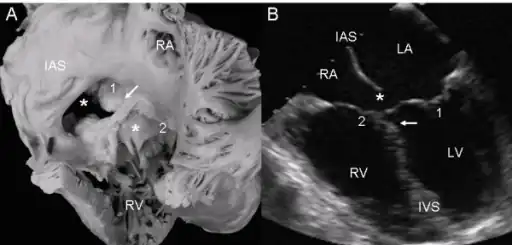

a,b)Atrioventricular septal defect with two separate atrioventricular valves.

a,b)Atrioventricular septal defect with two separate atrioventricular valves. -

Ultrasound showing a complete atrioventricular septal defect

Ultrasound showing a complete atrioventricular septal defect